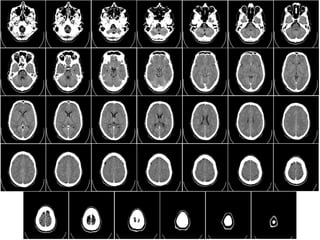

BASICS IN BRAIN CT SCAN

IL FAUT DETERMINER L'ÉTAGE Où VOUS ETES SUR LA TDM

POUR PRECISER LA LESION : Lésions intracrâniennes sus- et

sous-tentorielles !!

• L'intérieur du crâne est divisé en deux étages par la tente

du cervelet:

• L'étage sus-tentoriel qui contient les hémisphères

cérébraux et les structures profondes situées autour du

IIIéme ventricule.

• L'étage sous-tentoriel (que l'on pourrait aussi appeler

«fosse postérieure») qui contient le cervelet et le tronc

cérébral. Cet espace est limité supérieurement par la tente

du cervelet, inférieurement par le trou occipital et

latéralement par la boite crânienne.